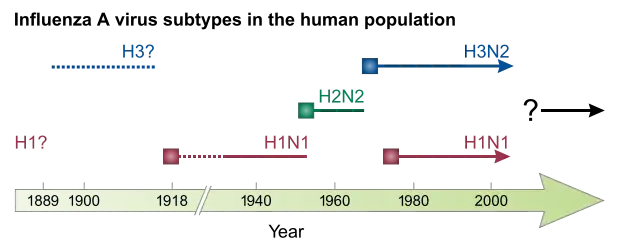

In a typical year, 5–15% of the population contracts influenza. There are 3–5 million severe cases annually, with up to 650,000 respiratory-related deaths globally each year. Deaths most commonly occur in high-risk groups, including young children, the elderly, and people with chronic health conditions. In temperate regions of the world, the number of influenza cases peaks during winter, whereas in the tropics influenza can occur year-round. Since the late 1800s, large outbreaks of novel influenza strains that spread globally, called pandemics, have occurred every 10–50 years. Five flu pandemics have occurred since 1900: the Spanish flu in 1918–1920, which was the most severe flu pandemic, the Asian flu in 1957, the Hong Kong flu in 1968, the Russian flu in 1977, and the swine flu pandemic in 2009.

IAV is responsible for most cases of severe illness as well as seasonal epidemics and occasional pandemics. It infects people of all ages but tends to disproportionately cause severe illness in the elderly, the very young, and those who have chronic health issues. Birds are the primary reservoir of IAV, especially aquatic birds such as ducks, geese, shorebirds, and gulls,[15][16] but the virus also circulates among mammals, including pigs, horses, and marine mammals. IAV is classified into subtypes based on the viral proteins haemagglutinin (H) and neuraminidase (N).[17] As of 2019, 18 H subtypes and 11 N subtypes have been identified. Most potential combinations have been reported in birds, but H17-18 and N10-11 have only been found in bats. Only H subtypes H1-3 and N subtypes N1-2 are known to have circulated in humans,[17] the current IAV subtypes in circulation being H1N1 and H3N2.[2] IAVs can be classified more specifically to also include natural host species, geographical origin, year of isolation, and strain number, such as H1N1/A/duck/Alberta/35/76.[1][9]

Antigenic shift is a sudden, drastic change in an influenza virus's antigen, usually HA. During antigenic shift, antigenically different strains that infect the same cell can reassort genome segments with each other, producing hybrid progeny. Since all influenza viruses have segmented genomes, all are capable of reassortment.[10][18] Antigenic shift, however, only occurs among influenza viruses of the same genus[19] and most commonly occurs among IAVs. In particular, reassortment is very common in AIVs, creating a large diversity of influenza viruses in birds, but is uncommon in human, equine, and canine lineages.[24] Pigs, bats, and quails have receptors for both mammalian and avian IAVs, so they are potential "mixing vessels" for reassortment.[17] If an animal strain reassorts with a human strain,[2] then a novel strain can emerge that is capable of human-to-human transmission. This has caused pandemics, but only a limited number have occurred, so it is difficult to predict when the next will happen.[1][9]

Outbreaks of influenza caused by novel influenza viruses are common.[19] Depending on the level of pre-existing immunity in the population, novel influenza viruses can spread rapidly and cause pandemics with millions of deaths. These pandemics, in contrast to seasonal influenza, are caused by antigenic shifts involving animal influenza viruses. To date, all known flu pandemics have been caused by IAVs, and they follow the same pattern of spreading from an origin point to the rest of the world over the course of multiple waves in a year.[1][9][32] Pandemic strains tend to be associated with higher rates of pneumonia in otherwise healthy individuals.[13] Generally after each influenza pandemic, the pandemic strain continues to circulate as the cause of seasonal influenza, replacing prior strains.[1] From 1700 to 1889, influenza pandemics occurred about once every 50–60 years. Since then, pandemics have occurred about once every 10–50 years, so they may be getting more frequent over time.[45]

From 1918 to 1920, the Spanish flu pandemic became the most devastating influenza pandemic and one of the deadliest pandemics in history. The pandemic, probably caused by H1N1, likely began in the USA before spreading worldwide by soldiers during and after the First World War. The initial wave in the first half of 1918 was relatively minor and resembled past flu pandemics, but the second wave later that year had a much higher mortality rate,[45] accounting for most deaths. A third wave with lower mortality occurred in many places a few months after the second.[23] By the end of 1920, it is estimated that about a third[11] to half of all people in the world had been infected, with tens of millions of deaths, disproportionately young adults.[45] During the 1918 pandemic, the respiratory route of transmission was clearly identified[23] and influenza was shown to be caused by a "filter passer", not a bacterium, but there remained a lack of agreement about influenza's cause for another decade and research on influenza declined.[54] After the pandemic, H1N1 circulated in humans in seasonal form[1] up until the next pandemic.[54]

During the Second World War, the US government worked on developing inactivated vaccines for influenza, resulting in the first influenza vaccine being licensed in 1945 in the United States.[1] ICV was discovered two years later in 1947.[17] In 1955, avian influenza was confirmed to be caused by IAV.[24] Four influenza pandemics have occurred since WWII, each less severe than the 1918 pandemic. The first of these was the Asian flu from 1957 to 1958, caused by an H2N2 strain[1][37] and beginning in China's Yunnan province. The number of deaths probably exceeded one million, mostly among the very young and very old.[45] Notably, the 1957 pandemic was the first flu pandemic to occur in the presence of a global surveillance system and laboratories able to study the novel influenza virus.[23] After the pandemic, H2N2 was the IAV subtype responsible for seasonal influenza.[1] The first antiviral drug against influenza, amantadine, was approved for use in 1966, with additional antiviral drugs being used since the 1990s.[4]

In 1968, H3N2 was introduced into humans as a result of a reassortment between an avian H3N2 strain and an H2N2 strain that was circulating in humans. The novel H3N2 strain first emerged in Hong Kong and spread worldwide, causing the Hong Kong flu pandemic, which resulted in 500,000–2,000,000 deaths. This was the first pandemic to spread significantly by air travel.[3][23] H2N2 and H3N2 co-circulated after the pandemic until 1971 when H2N2 waned in prevalence and was completely replaced by H3N2.[3] In 1977, H1N1 reemerged in humans, possibly after it was released from a freezer in a laboratory accident, and caused a pseudo-pandemic.[23][54] Whether the 1977 "pandemic" deserves to be included in the natural history of flu pandemics is debatable.[45] This H1N1 strain was antigenically similar to the H1N1 strains that circulated prior to 1957. Since 1977, both H1N1 and H3N2 have circulated in humans as part of seasonal influenza.[1] In 1980, the current classification system used to subtype influenza viruses was introduced.[58]

At some point, IBV diverged into two lineages, named the B/Victoria-like and B/Yamagata-like lineages, both of which have been circulating in humans since 1983.[17] In 1996, HPAI H5N1 was detected in Guangdong, China[24] and a year later emerged in poultry in Hong Kong, gradually spreading worldwide from there. A small H5N1 outbreak in humans in Hong Kong occurred then,[30] and sporadic human cases have occurred since 1997, carrying a high case fatality rate.[15][39] The most recent flu pandemic was the 2009 swine flu pandemic, which originated in Mexico and resulted in hundreds of thousands of deaths.[23] It was caused by a novel H1N1 strain that was a reassortment of human, swine, and avian influenza viruses.[16][4] The 2009 pandemic had the effect of replacing prior H1N1 strains in circulation with the novel strain but not any other influenza viruses. Consequently, H1N1, H3N2, and both IBV lineages have been in circulation in seasonal form since the 2009 pandemic.[1][23][24]